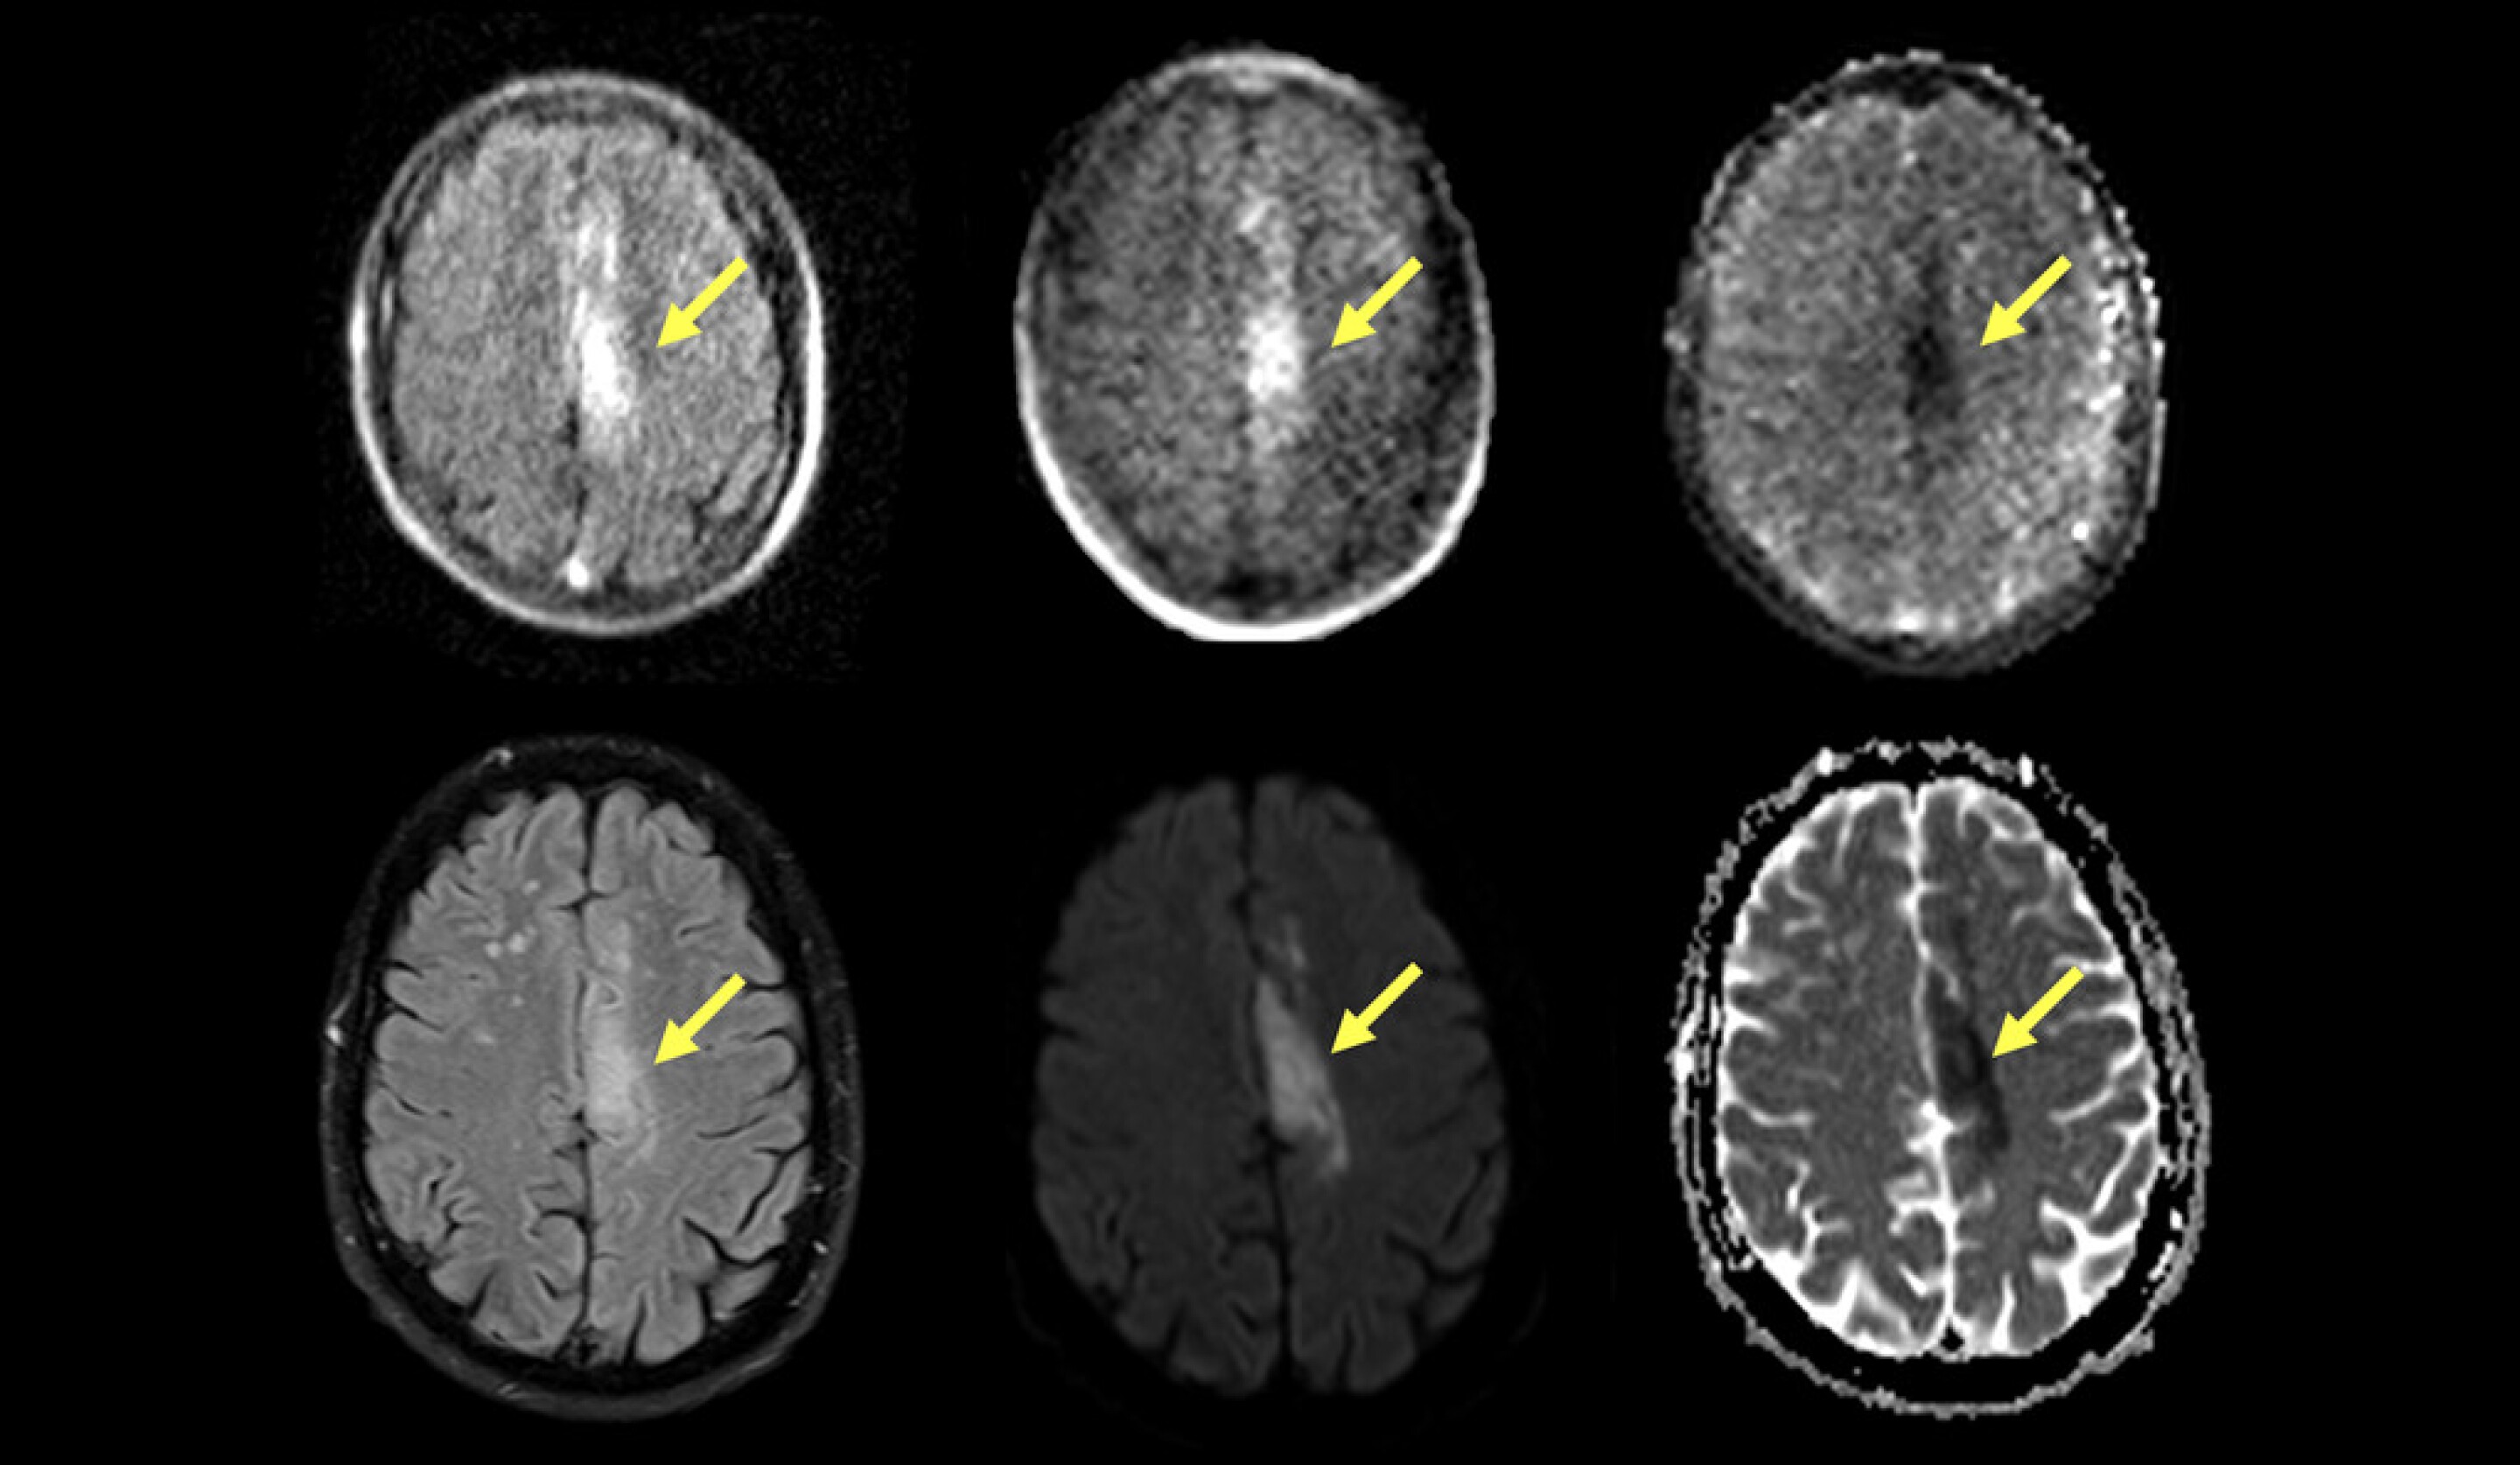

Portable MRI Can Accurately Detect Most Common Form Of Stroke